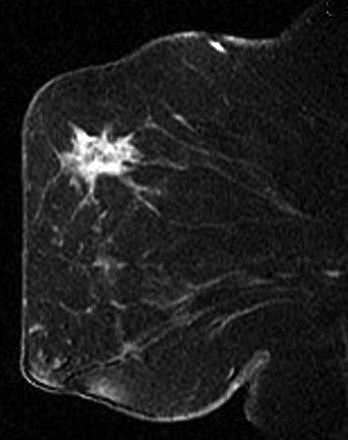

| A 69-year-old woman who presented with palpable left axillary nodes positive for metastatic mammary cancer with no primary cancer identified on mammography or physical examination. Sagittal T1-weighted contrast-enhanced MRI of left breast shows spiculated, irregular, heterogeneously enhancing mass. Biopsy yielded invasive ductal cancer. Bartella L, Liberman L, Morris EA, and Dershaw DD, "Nonpalpable Mammographically Occult Invasive Breast Cancers Detected by MRI" (AJR 2006; 186:865-870). |